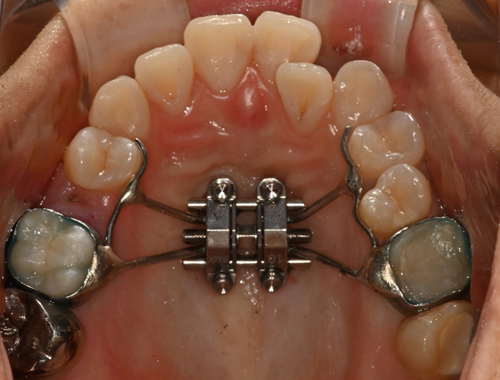

비수술 악궁확장 치료 MARPE (Miniscrew-assisted rapid palatal expansion)

덧니의 근본적인 원인은 치아 크기에 비해서 뼈의 크기가 작기 때문입니다.

청소년기가 지나간 성인에서는 뼈의 크기를 늘리기 어렵지만 이지민 대표원장은 가능합니다.

확장 전

확장 전

이지민 원장은 성인 비발치 교정의 핵심인 비수술 악궁 확장 가능성을, 직접 연구한 논문 결과를 바탕으로 사전에 정밀 분석·예측합니다.